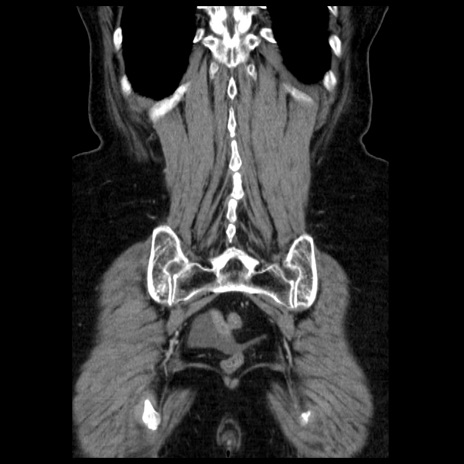

症例13(冠状断像)

【身体所見】意識清明、BP 121/72mmHg、P 74bpm、SpO2 100%(RA)、腹部:平坦・軟、腸雑音ほぼ聴取せず。下腹部・心窩部・臍左上に圧痛あり。反跳痛なし。